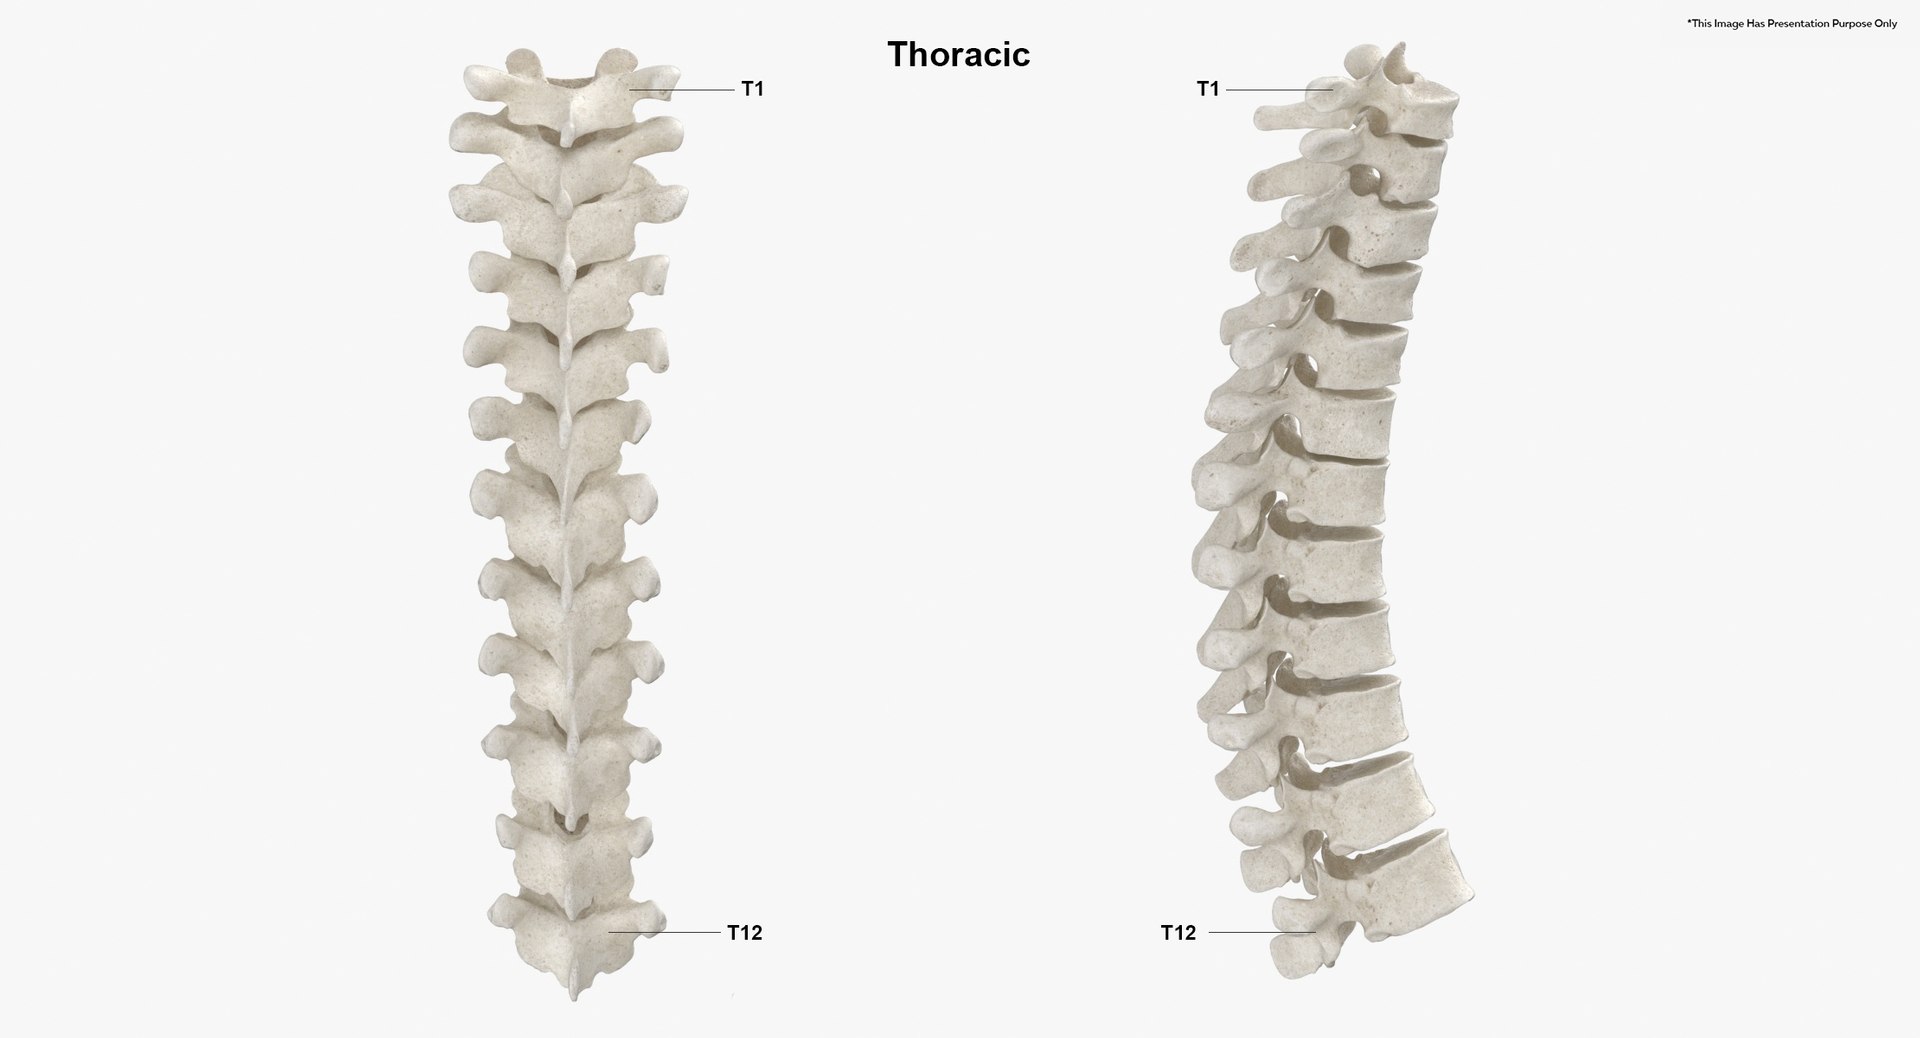

Структура позвоночника: сегменты и тазовые отделы в фотографиях